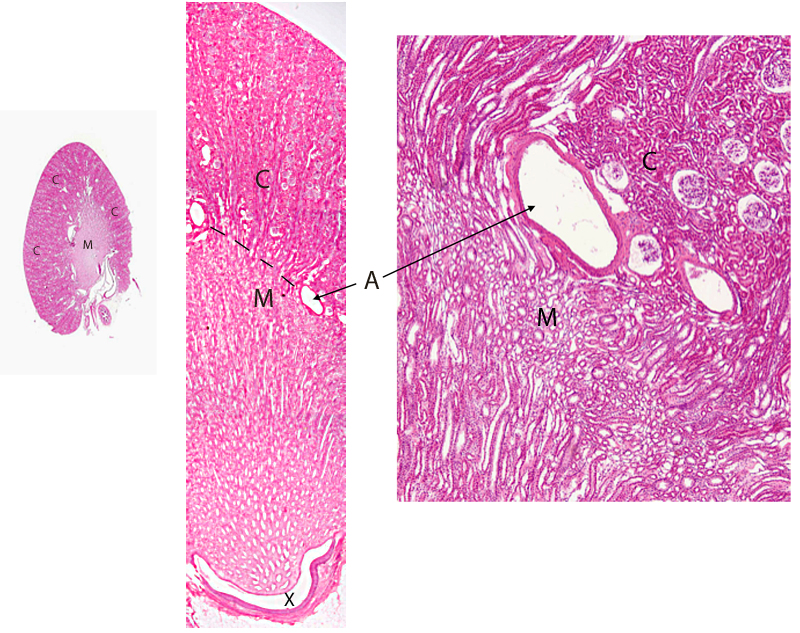

Example of a unilobar kidney (no slide)

Kidneys of small animals such as the rabbit and cat consist of a single lobe. Larger animals require more functional tissue than can be placed in a single lobe and thus have multilobar kidneys. This image of a unilobar kidney demonstrates the basic organization of cortical and medullary regions. The arcuate arteries (A) mark the junction between the cortex (C) and medulla (M). The outer cortex is covered by the capsule. The calyx (X) is a recess of the renal pelvis where urine collects. The lumen of the calyx is the clear space between the papilla of the pyramid and the ureter. Except for the calyx region, the medulla of a unilobar kidney is surrounded by cortical tissue.

Three maginifications of the corticomedullary region of a unilobar kidney. H&E stain.